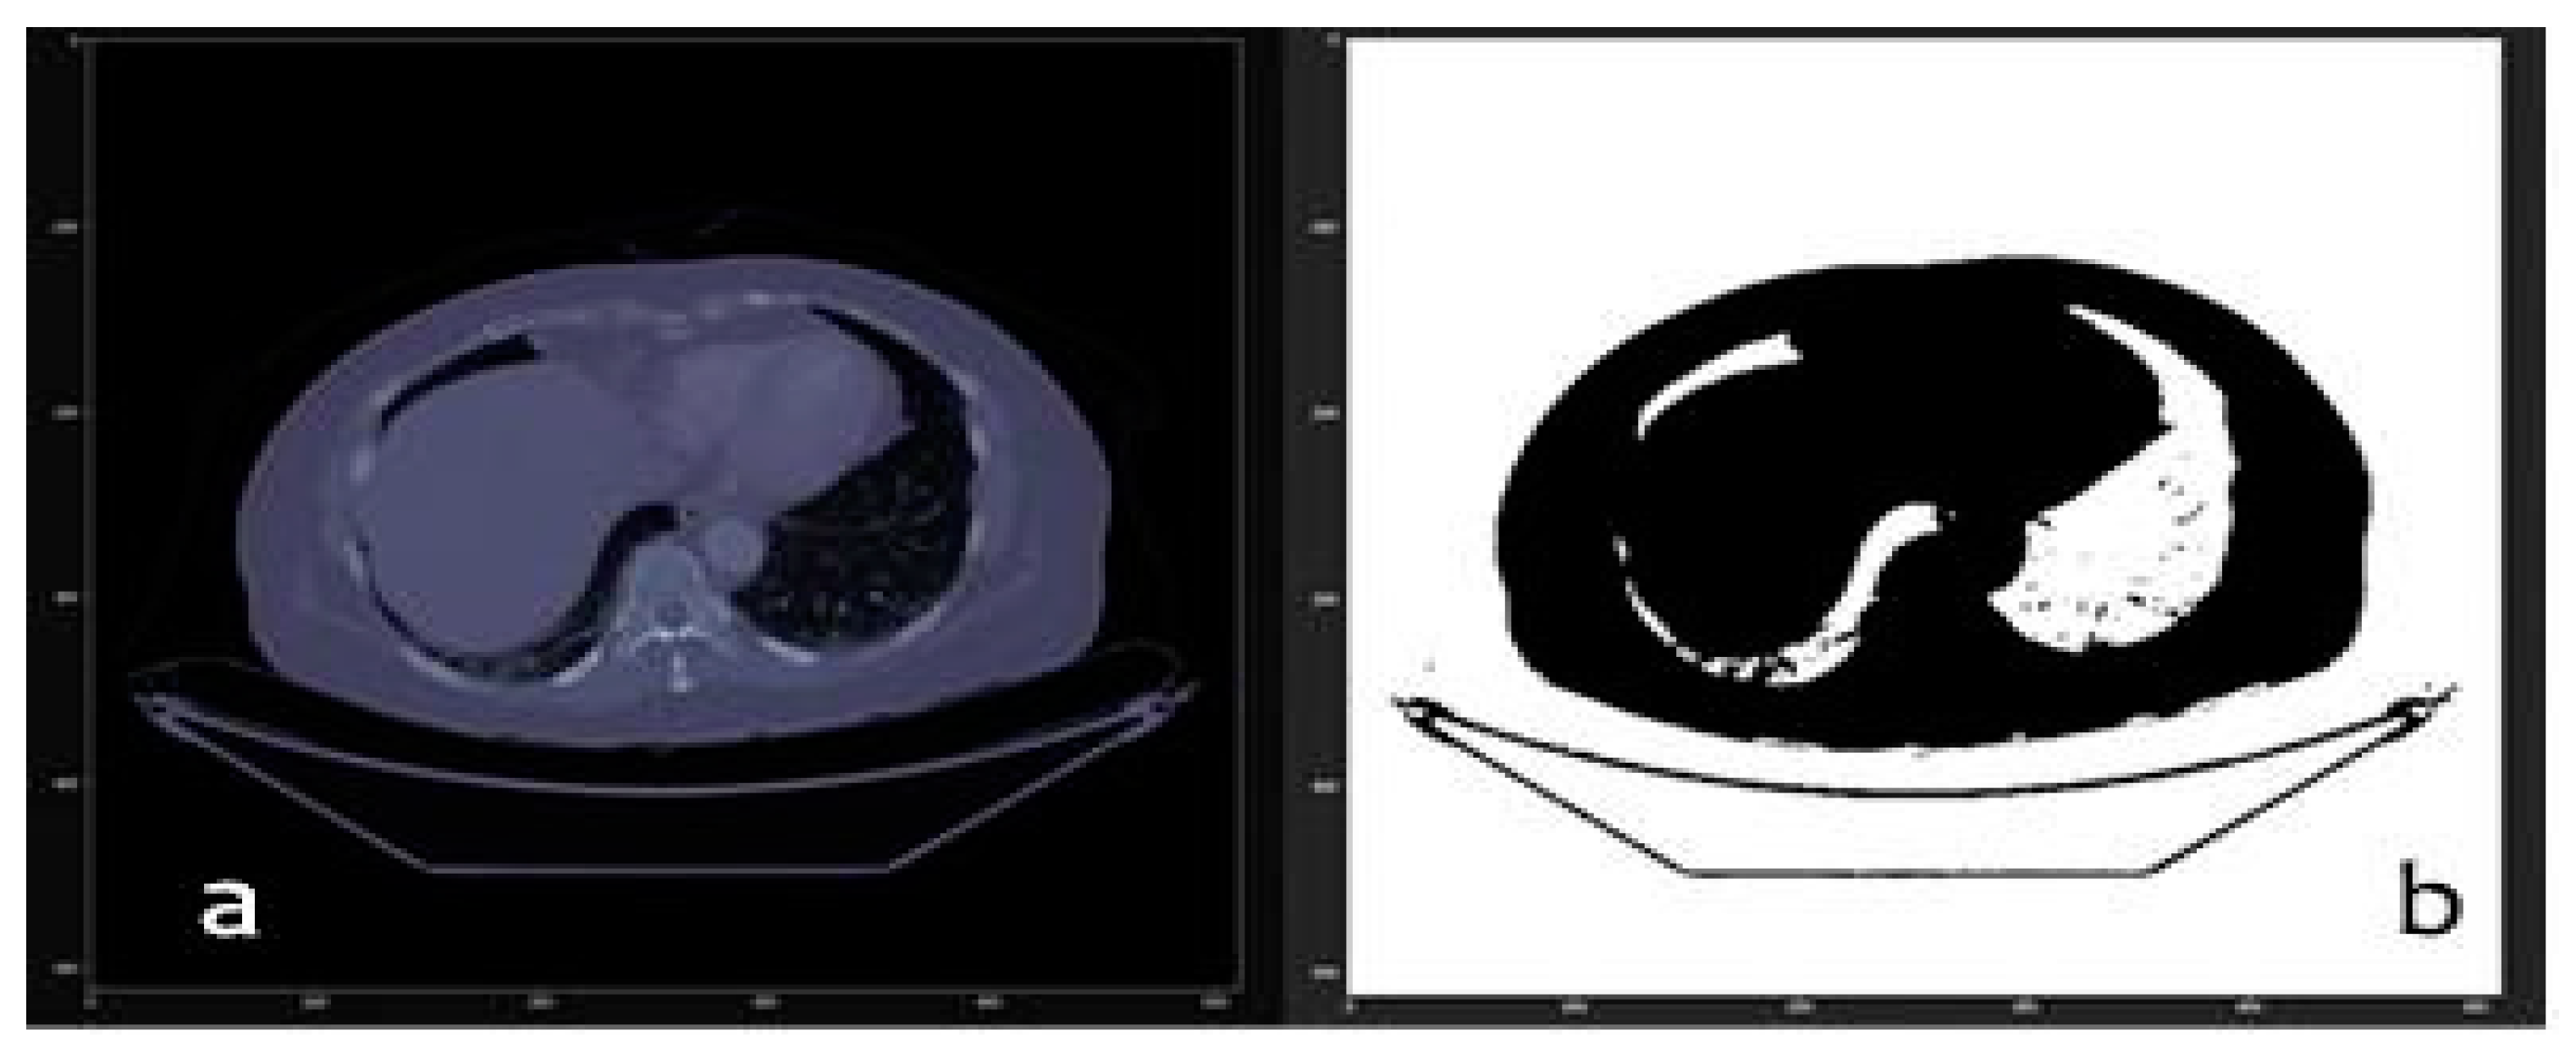

3.1. From dicom to 3D Models with Automatic Segmentation

2.3. Computer Vision Algorithms

- Processed by thresholding: based on keeping the voxels whose intensities are within a fixed range, and setting the rest to a fixed value that is interpreted as the background of the image. This process is useful for separating structures when no different regions with similar intensities exist.

- Morphological processing: based on form, such as erosion and dilation.